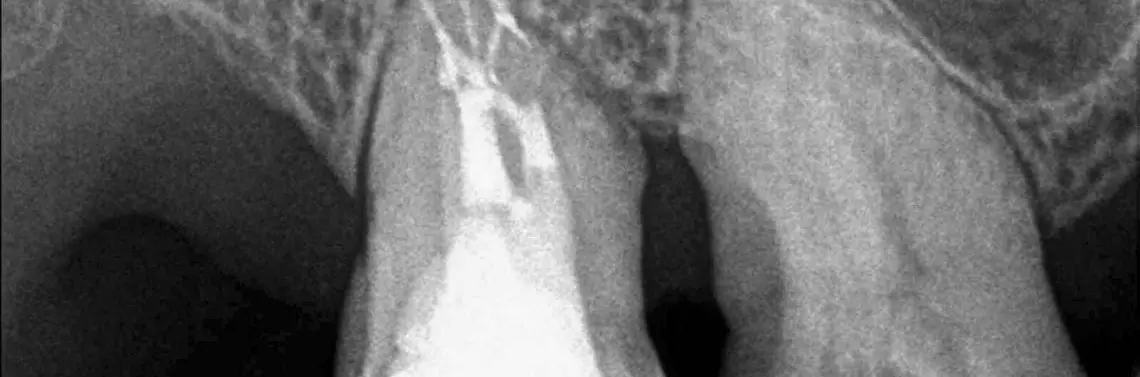

Pozostawienie miazgi w kanale zwykle oznacza kłopoty. W najlepszym wypadku u pacjenta pojawi się samoistny ból, ale to tylko jedna z wielu dolegliwości, które mogą dokuczać pacjentowi w takiej sytuacji. Co zrobić, by temu zapobiec? Dokładnie usunąć miazgę z kanałów.

Jeśli w kanale pozostanie żywa lub ledwo żywa, ale niezainfekowana miazga, możemy spodziewać się braku dolegliwości bólowych lub obecności dolegliwości bólowych samoistnych, a z czasem najprawdopodobniej dojdzie do obliteracji kanału. Pozostawienie miazgi zainfekowanej może się jednak skończyć w najlepszym wypadku samoistnymi dolegliwościami bólowymi. Niestety, gama dolegliwości, które pacjent może zgłaszać, jest spora. Zmiana okołowierzchołkowa widoczna na zdjęciu, bolesność uciskowa w rzucie wierzchołka, przetoka...